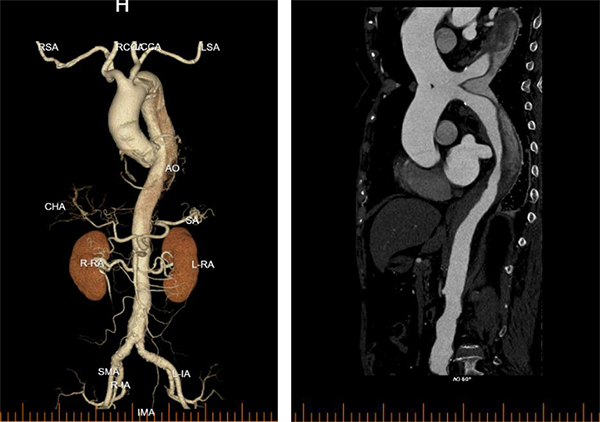

李阿姨今年79岁了,2026年2月27日一早起床,突然觉得胸背剧烈疼痛难忍,自己觉得可能心脏出问题了,家人赶紧拨打120送到东方医院急诊科。急诊科副主任张志辰接诊后依据丰富的临床经验初步考虑存在主动脉夹层可能,遂立即进行胸腹CT检查,并完成急查主动脉CTA,确诊患者为主动脉夹层B型!患者病情极为凶险,撕裂的主动脉如同一颗随时可能引爆的“炸弹”,时刻威胁着患者的生命。时间就是生命,必须立即启动急诊手术!

术中,周围血管科团队凭借丰富的临床经验和精湛的手术技艺,精准定位主动脉破口,成功植入覆膜支架,完整修复了撕裂的血管内膜,隔绝了假腔血流。术后造影显示支架位置良好,主动脉破口完全封闭,手术取得圆满成功。